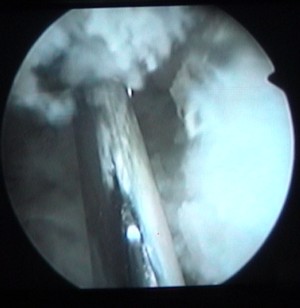

enlèvement d'un ménisque |